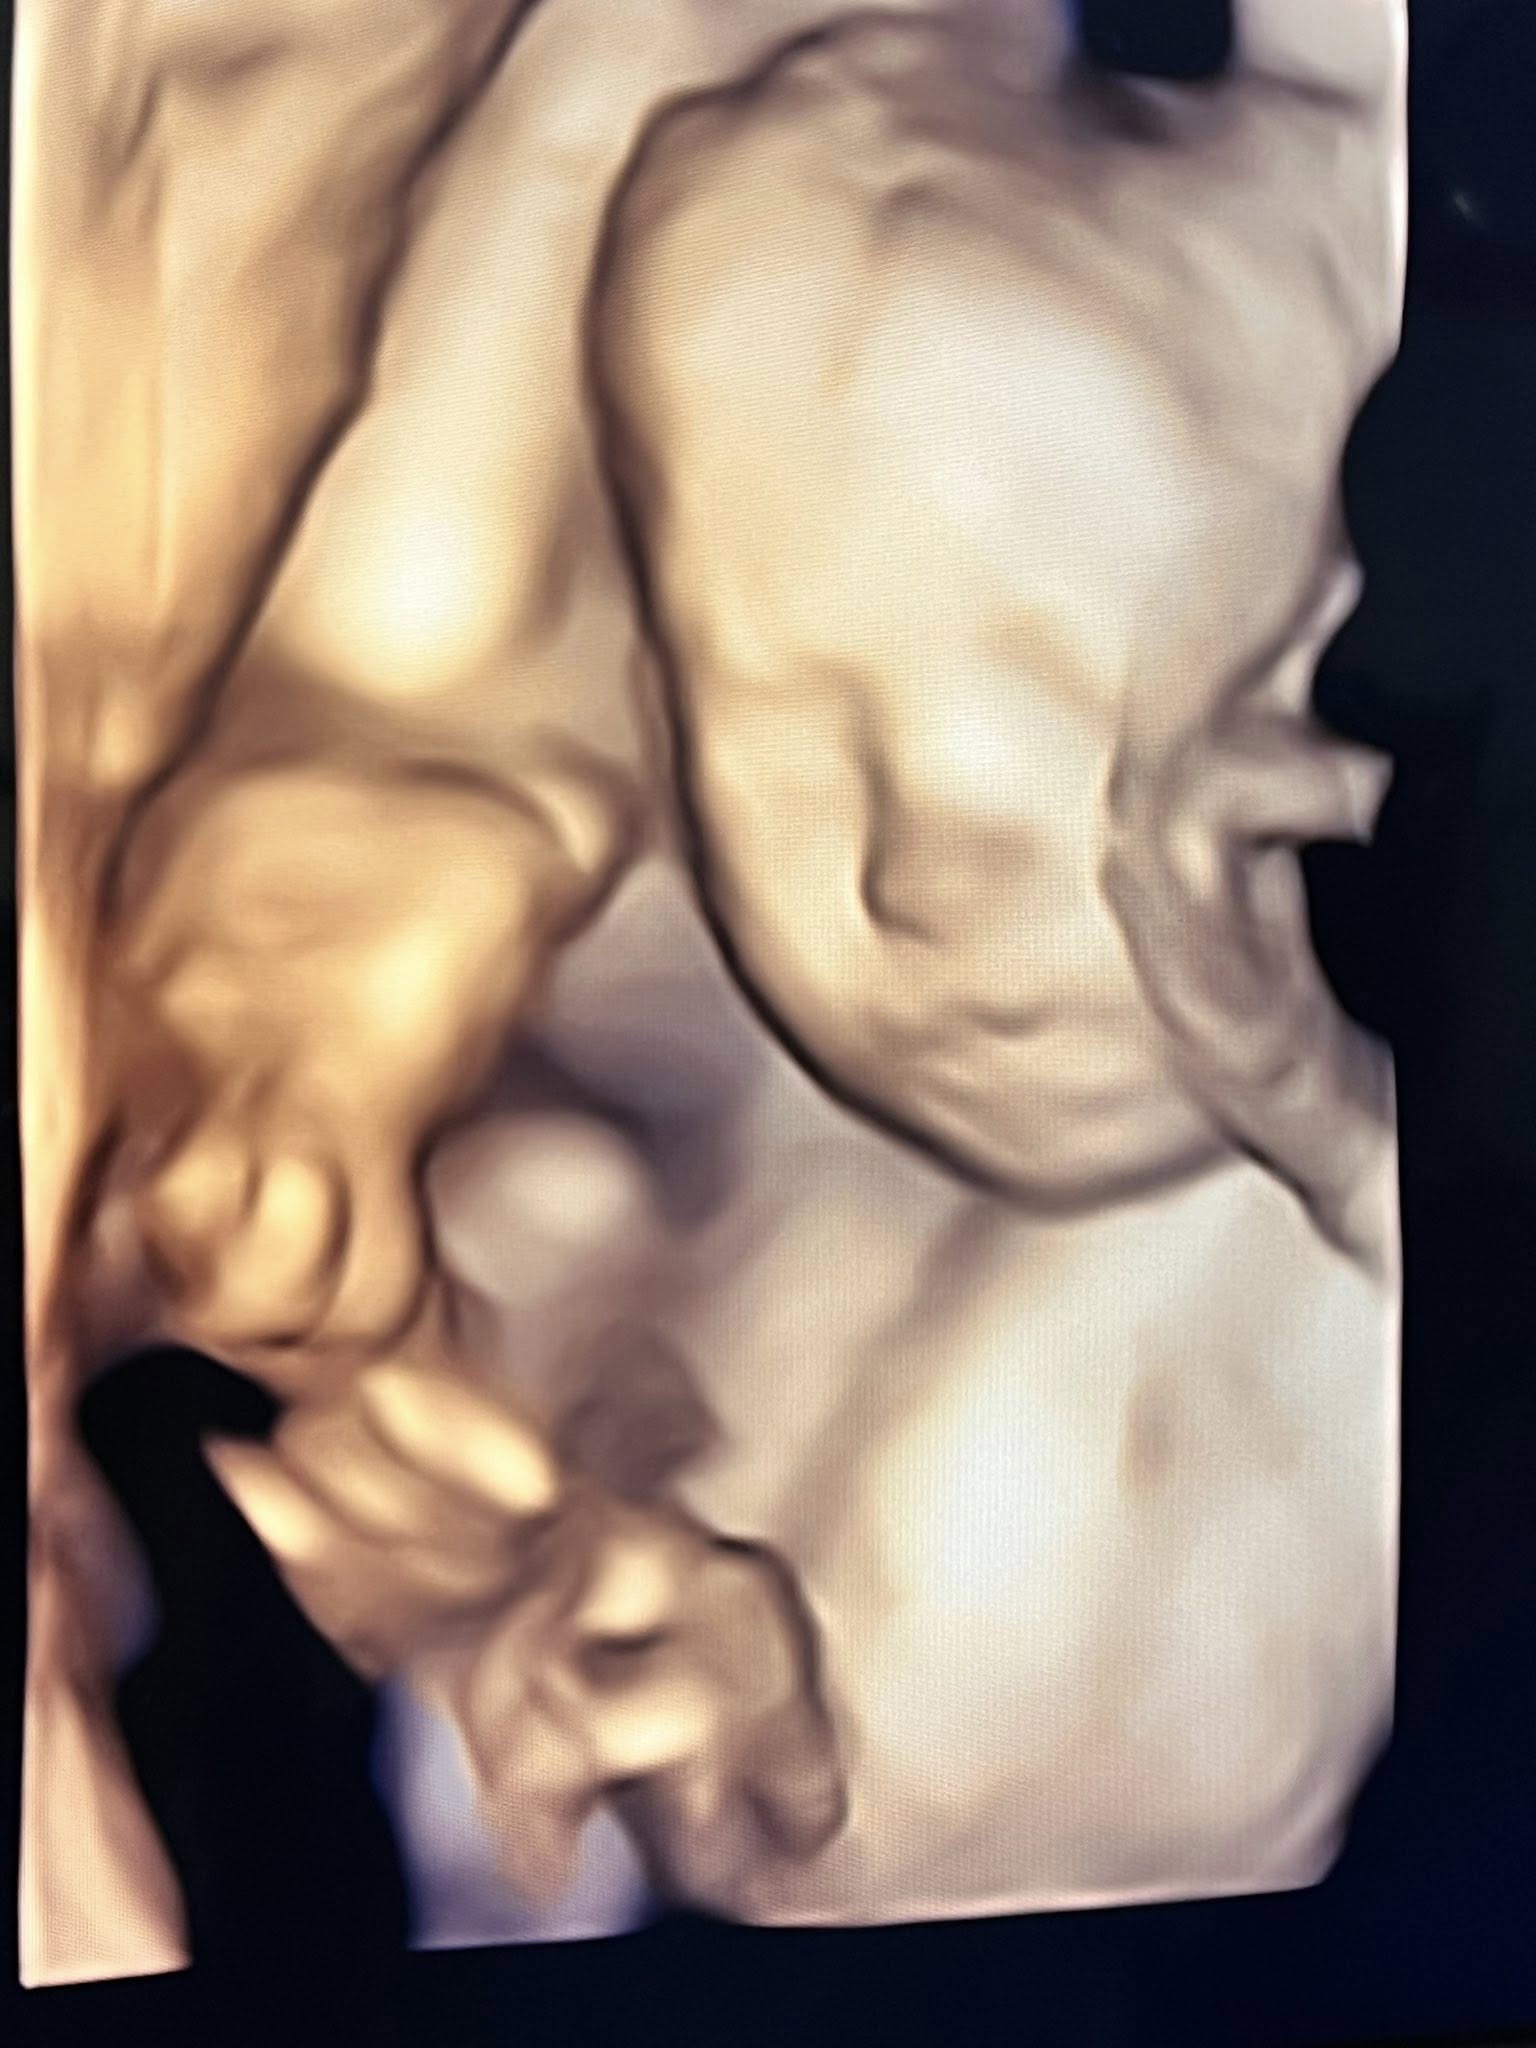

จากภาพอัลตราซาวด์เผยให้เห็นเค้าโครงใบหน้าของน้องมีเมตตาอย่างชัดเจน นอนยิ้มหวานละมุน แถมจมูกโด่งสะดุดตา เรียกได้ว่าน่ารักน่าชังตั้งแต่อยู่ในท้อง โดยพ่อเจมส์เขียนแคปชันด้วยความเอ็นดูว่า “แม่หนูมีเมตตาของฉัน จมูกโด่ง ยิ้มหวาน” พร้อมอัปเดตว่า คุณหมอกล้วย แพทย์ผู้ดูแลครรภ์ครูก้อย ยืนยันว่าลูกน้อยแข็งแรงสมบูรณ์ พัฒนาการเป็นไปตามเกณฑ์ทุกด้าน ก่อนจะปิดท้ายด้วยมุกขำ ๆ สไตล์คุณพ่อว่า “สินค้าเด็กเข้าได้เลยครับ ( ฮาาา…. )” ทำเอาแฟน ๆ เข้ามากดไลก์และคอมเมนต์ชื่นชมความน่ารักของน้องมีเมตตาอย่างล้นหลาม

ด้านคุณแม่คนสวย ครูก้อย นัชชา ก็ไม่น้อยหน้า โพสต์คลิปอัลตราซาวด์ของลูกสาวเช่นกัน พร้อมแคปชันสั้น ๆ ว่า “แม่ว่า…ดูทรงยาว ทรงคมนะ” งานนี้หลายคนอดเดาไม่ได้ว่า น้องมีเมตตาน่าจะได้ความสูงยาวและเค้าโครงคม ๆ มาจากพ่อเจมส์และแม่ก้อยแบบเต็ม ๆ

ก่อนหน้านี้ ครูก้อยเคยให้สัมภาษณ์ว่า การตั้งครรภ์ครั้งนี้แพ้ท้องน้อยมาก อารมณ์ดี มีความสุขตลอด เนื่องจากมีการเตรียมความพร้อมอย่างรอบด้านตั้งแต่ก่อนตั้งครรภ์ ทั้งการจัดการเรื่องงาน โภชนาการ และการออกกำลังกาย เนื่องจากมีภาวะมีบุตรยากจึงมีความเตรียมความพร้อมเป็นพิเศษ เมื่อทุกอย่างลงตัวก็ส่งผลให้ลูกน้อยในท้องอารมณ์ดีตามไปด้วย จนเห็นได้จากภาพอัลตราซาวด์ที่น้องมีเมตตานอนยิ้มหวาน น่าเอ็นดูตั้งแต่อยู่ในท้อง